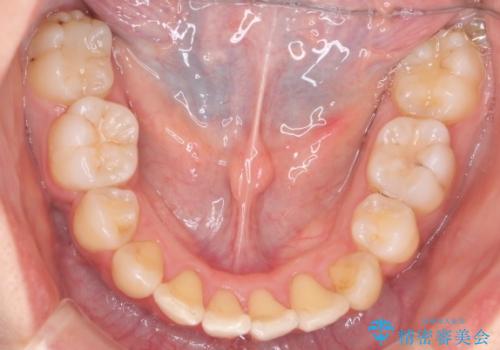

ガタガタの抜歯矯正を裏側ワイヤーを使っての目立たない矯正

- 2年2ヶ月

- 八重歯とガタガタを主訴に来院されました。

目立たないワイヤー矯正を希望されたので、上下左右のはを1本ずつ抜歯して、ハーフリンガル(上顎だけ裏側)にて矯正をすることにしました。